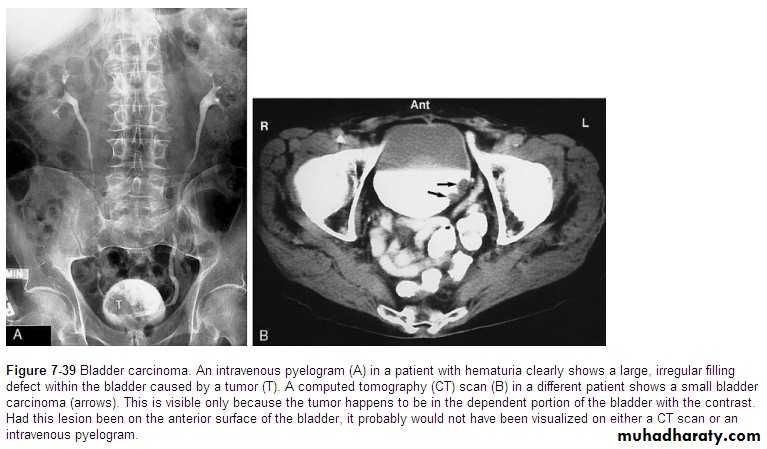

• Bladder tumors

• The bladder is the most frequent site for neoplasm in the urinary tract. Almost all(95%) are transitional cell carcinoma. They vary in shape: papillary, sessile or flat plaque. US is the initial imaging investigation. The main role of urography (IVU or CT urography) is to demonstrate any other lesions in the upper tracts (PCS and ureters), as transitional cell carcinomas are often multifocal.• US: soft tissue masses protruding into the fluid-filled bladder or as localized bladder wall thickening, but the technique is poor for detecting extravesical spread. There may be echogenic foci on the tumor surface due to calcific encrustation.

• IVU: is less sensitive than US in detecting small bladder masses, but if the mass is a large enough, a filling defect in the bladder may be seen.